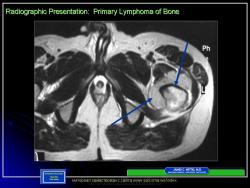

Варианты злокачественной лимфомы: 1.Первичная костная опухоль без каких-либо признаков наличия её в других тканях. 2. Лимфомы мягких тканях 3.Первичный лимфоматоз мягких тканей с метастазами в кости.

Более чем в 80% случаев лимфома кости локализуется в длинных трубчатых костяк нижних конечностей. Поражаются также подвздошные кости, позвонки, лопатки, кости черепа, ребра, грудина и надколенник.

Большинство авторов указывают, что у лимфомы кости нет патогномоничных рентгенологических признаков. В начальных фазах развития рентгенодиагностика лимфомы кости весьма затруднительна. Реакция периоста наблюдается редко и не имеет каких-либо характерных особенностей. Кортикальный слой разрушается на большем или меньшем протяжении, но не расплавляется, как при остеолитических опухолях типа остеогенных сарком. Классическим проявлением считается мелконоздреватая деструкция, создающая картину пористой, рыхлой, пятнистой кости. Мелкоочаговая деструкция — сравнительно ранний симптом и не всегда улавливается рентгенологически. При прогрессировании процесса мелкие очаги сливаются в обширные литические участки, которые при первичном обследовании больных являются причиной значительных диагностических трудностей [Нечволодова О. Л., 1971]. Иногда на фоне очага отмечается ячеистый рисунок с плотными четкими перегородками. В плоских костях преобладает литический компонент, лишь иногда по периферии сохраняются участки костной ткани с характерным разволокнением и ноздреватым рисунком.